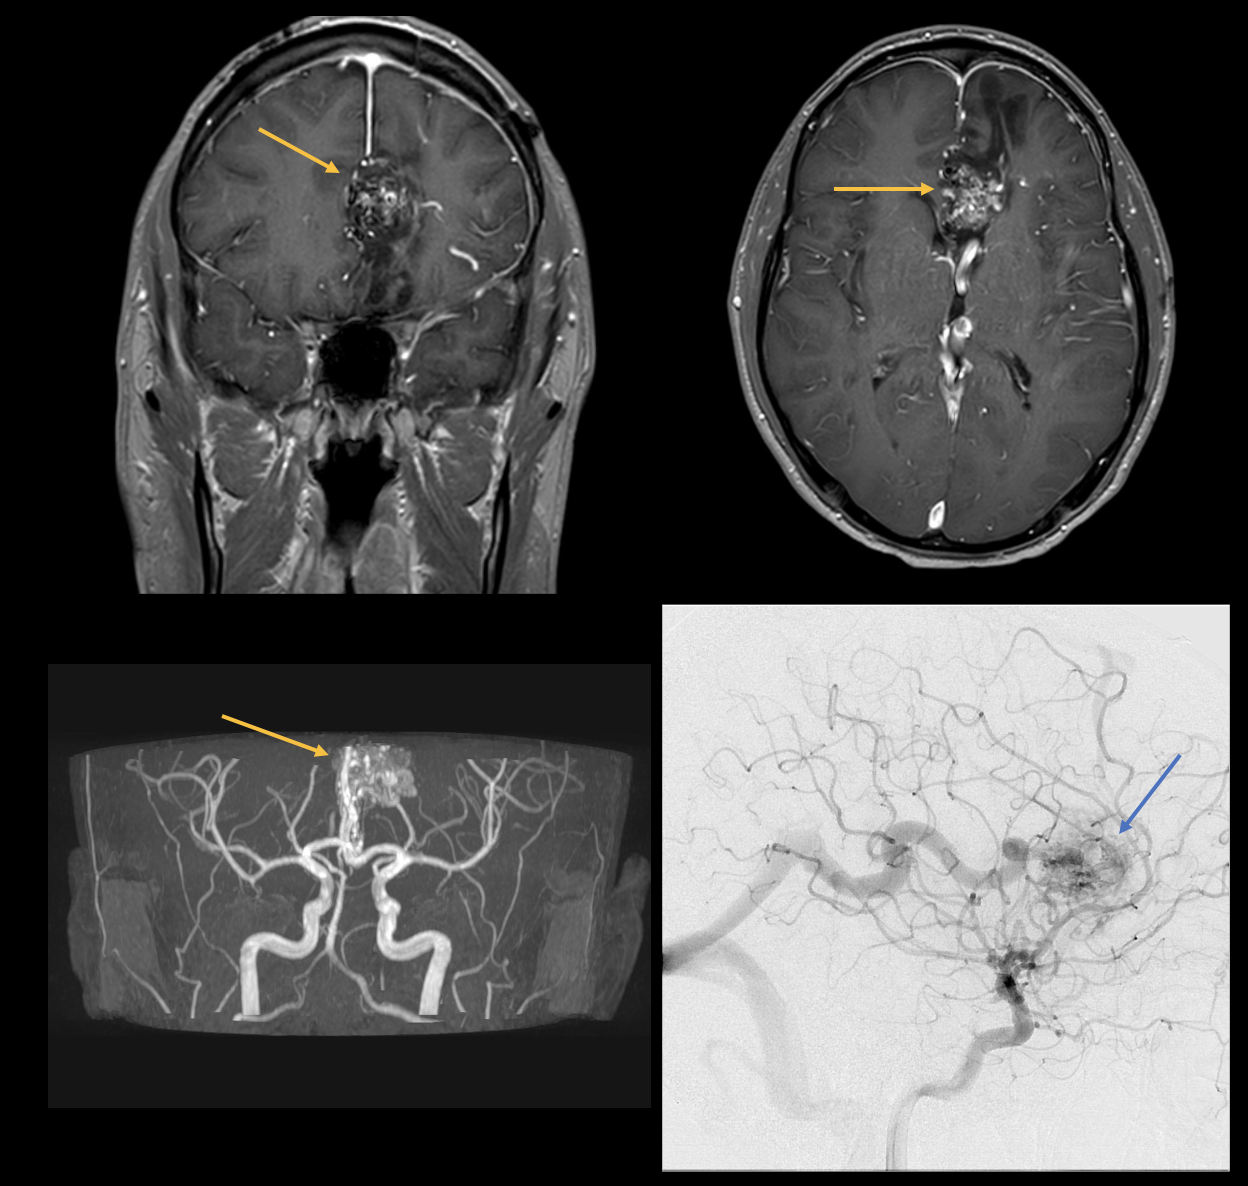

Bei einer 47-jährigen Patientin (siehe Abbildungen) wurde ein Akustikusneurinom auf der rechten Seite festgestellt, das zu einem Hörsturz führte.

Bild 2: MRT der hinteren Schädelgrube in T2- und T1-Wichtung. Hier zu sehen ist eine T2-W-isointense Raumforderung im meatus acusticus internus, vereinbar mit einem Akustikusneurinom.